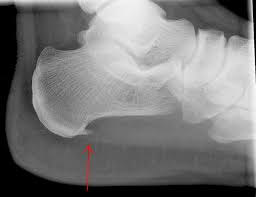

구조적으로 발바닥의 아치가 정상보다 낮아 흔히 평발로 불리는 편평족이나, 아치가 정상보다 높은 요족(cavus) 변형이 있는 경우 족저근막염의 발생 가능성이 높다. 또한 다리 길이의 차이, 발의 과도한 회내(발뒤꿈치의 바깥쪽 회전과 발목의 안쪽 회전의 복합 운동) 변형, 하퇴부 근육의 구축 또는 약화 등이 있는 경우에도 족저근막염을 유발할 수 있다. 족저근막의 발뒤꿈치뼈 부착 부위에 뼛조각이 튀어나온 사람들 중 일부에서 족저근막염이 발생하기도 한다.

전형적인 증상은 아침에 일어나 처음 발을 디딜 때 느껴지는 심한 통증이 특징적이지만, 모두 같은 증상을 겪는 것은 아니다. 통증은 주로 발꿈치 안쪽에 발생하는 경우가 대부분이고 발뒤꿈치뼈 전내측 종골 결절 부위를 누르면 통증이 발생하기도 한다. 발가락을 발등 쪽으로 구부리면 통증이 심해지기도 한다.